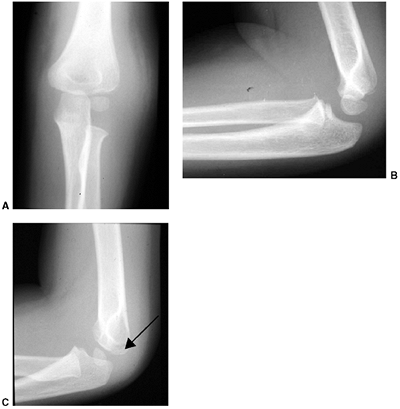

treated with an above-elbow cast for 3 weeks. Any medial buckling or

impaction of the medial metaphysis may indicate a fracture that

requires reduction. This fracture is a diagnostic trap, because the

collapse of the medial column may be very subtle (Fig. 33.17).

The Baumann angle, or the medial epicondylar epiphyseal angle, should

be carefully measured bilaterally; more than 10 degrees of varus

impaction warrants closed reduction and percutaneous pinning (CRPP). It

is difficult to maintain the reduction by cast immobilization alone,

and residual deformity will not remodel (128).